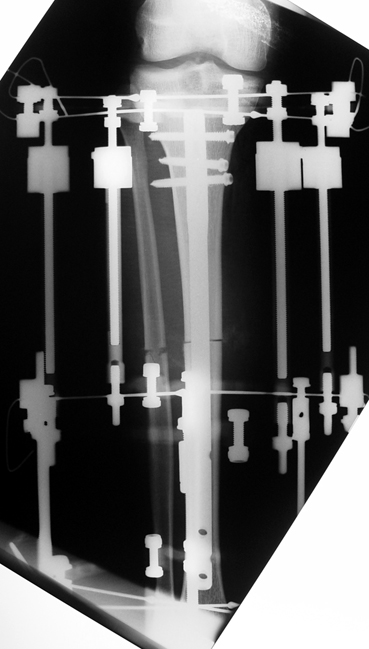

3. POSTTRAUMATIC LOWER LIMB SHORTNESS (MALUNION)

This type of shortness occurs after a fracture heals in a shortened position. Most cases are seen in adults and can be treated with one lengthening operation. Additional deformities can be corrected simultaneously. Most of these cases can be treated with lengthening over nail or just corrections and intramedullary nailing.